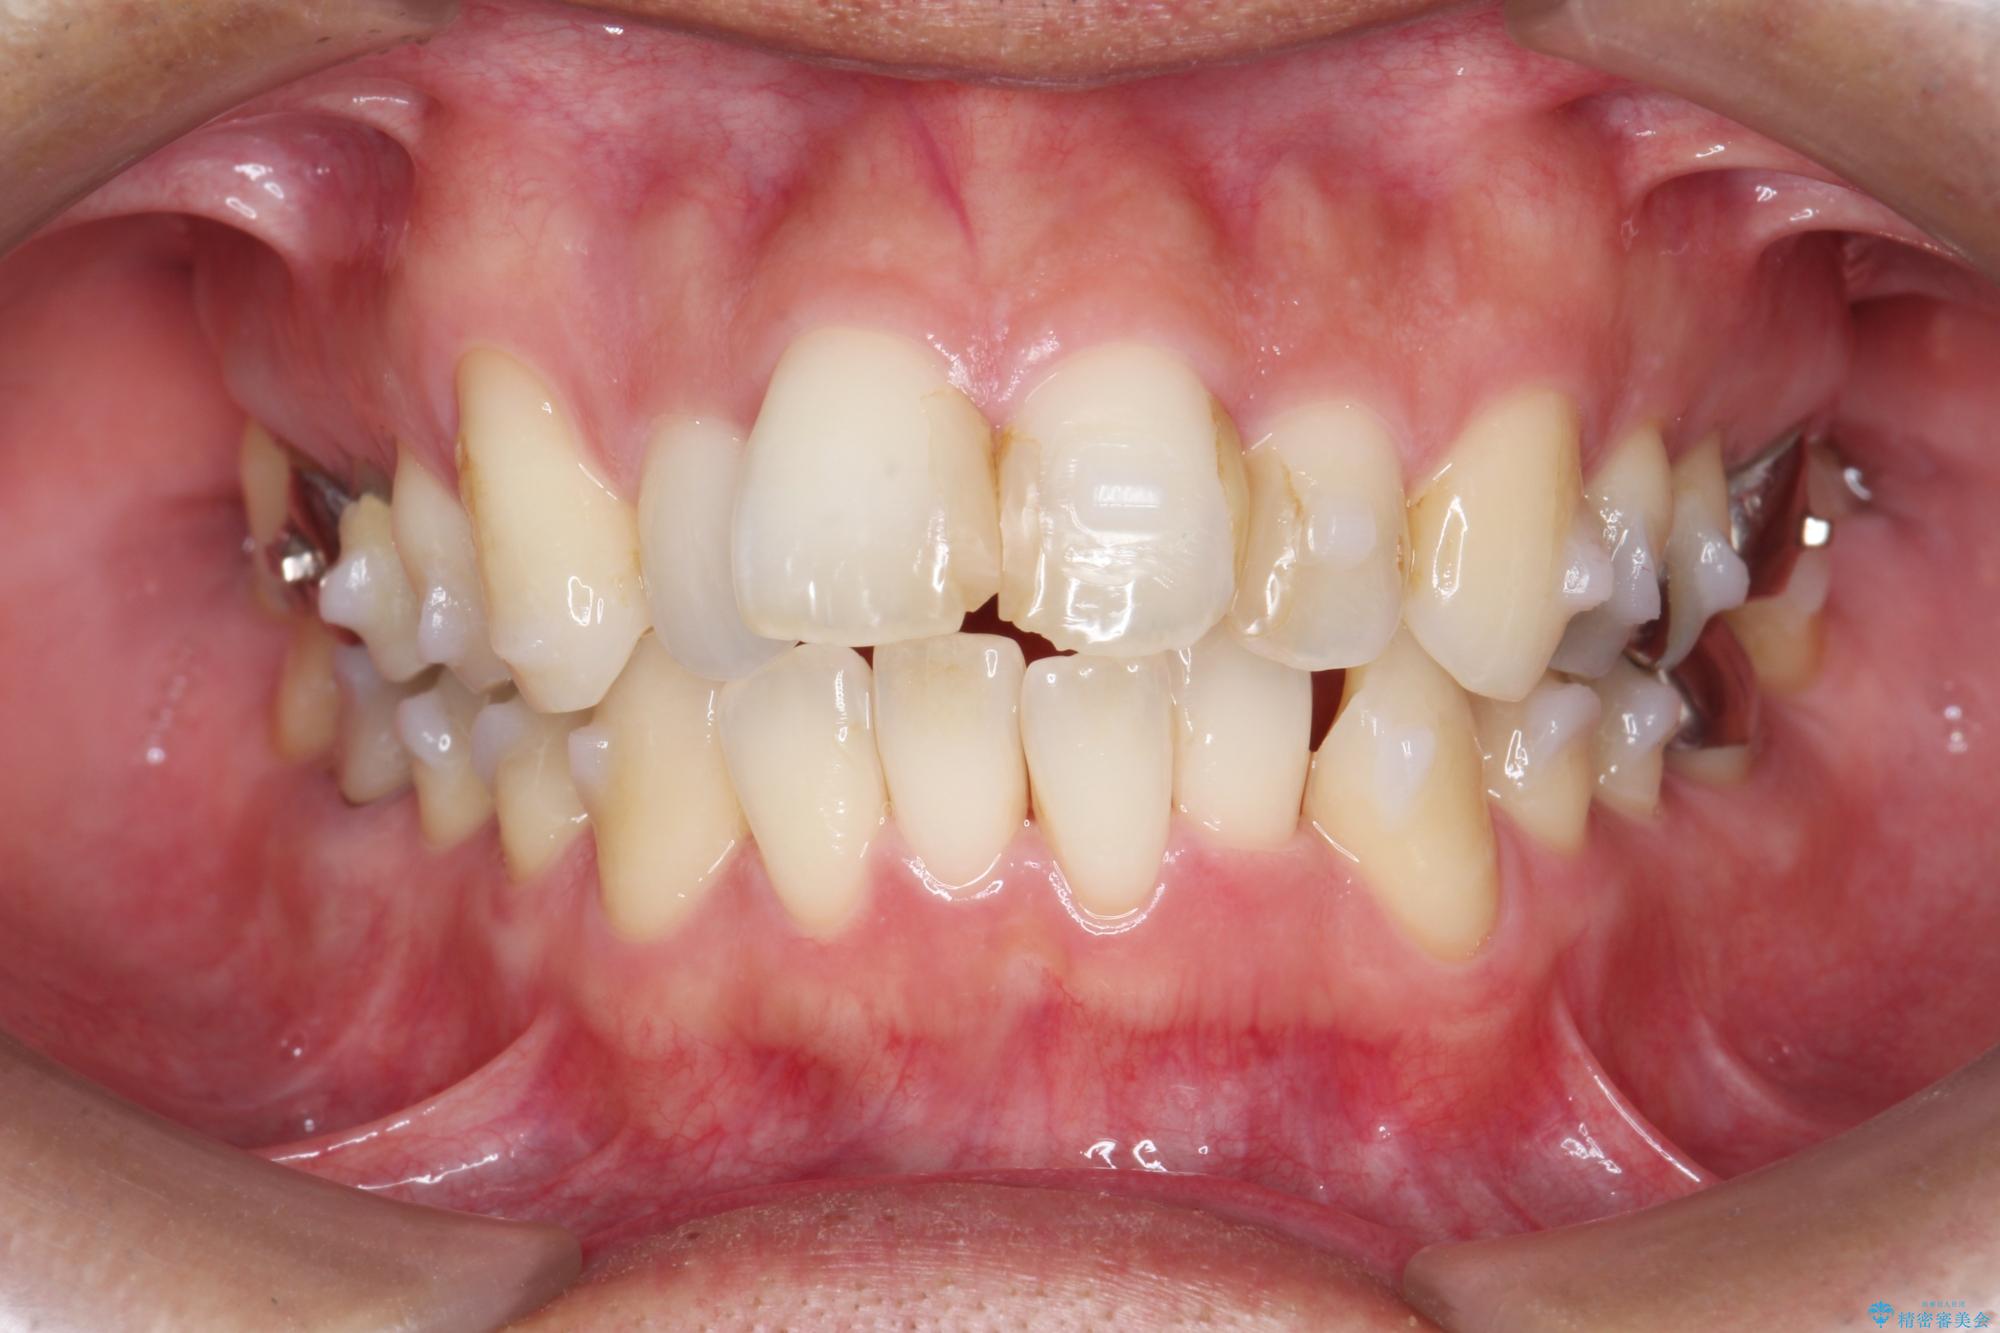

- 突き出た前歯の角度の改善と虫歯治療の改善を求めて来院されました。

虫歯を除去したのち、マウスピース矯正治療を行い、歯並びやがたつきを改善したのち、セラミックに置き換えることで審美性の向上を計画します。